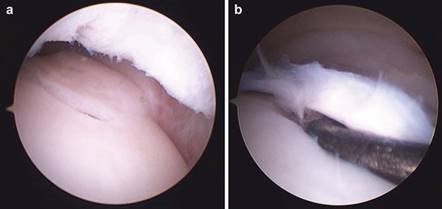

In cases of end-stage hallux rigidus, first MTP arthrodesis yields excellent, predictable outcomes. A dorsal longitudinal incision is made just medial to the EHL tendon. The joint is exposed, and aggressive cheilectomy is performed to remove all dorsal, medial, and lateral osteophytes. The remaining articular cartilage on the metatarsal head and the base of the proximal phalanx is resected using cup-and-cone reamers, which allow for infinite adjustment of the joint position prior to fixation.

Clinical & Radiographic Imaging Archive